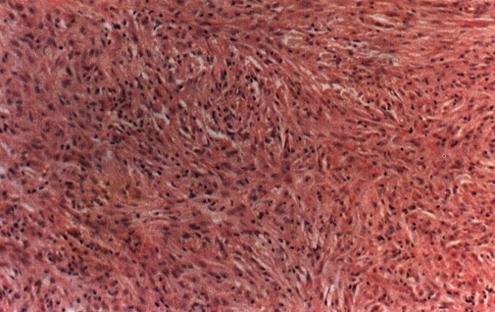

常在原先的皮损处,又出现细菌增殖,因此开始时仅见陈旧的肉芽肿仍处于消退状态。中期细菌的活性变化无常,组织学的变化明显。因此细菌学和组织学的发现可能不一致。特别在后期,细胞的活动性很明显。复发时有一部分图象呈组织样麻风瘤病变(照片11),其余与各型麻风相同。组织学检查可证明复发,但无助于确定复发是由耐药菌还是持久菌所引起。

照片11 组织样麻风瘤(HL)

有大量巨噬细胞浸润,呈方向性排列,未见泡沫细胞。